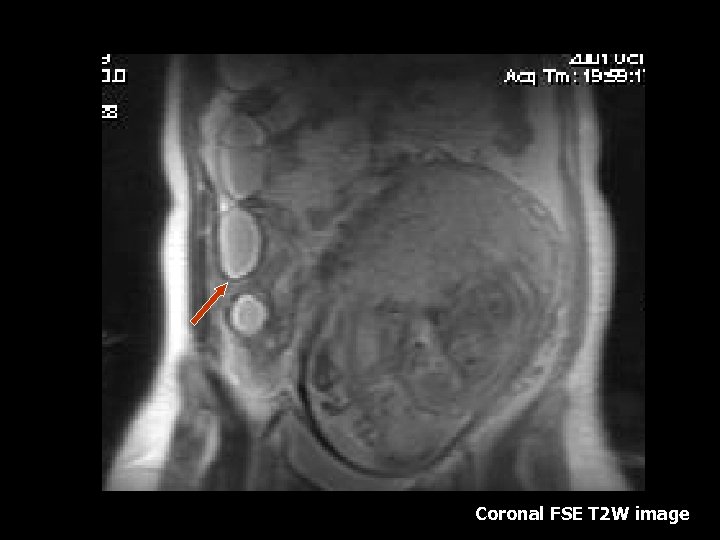

Ovarian Torsion • Fifth most common gynecologic diagnosis(8). • Symptoms – Abdominal pain, nausea and vomiting(8). • Early diagnosis can salvage ovarian function(10%)(8). • Torsion produces circulatory stasis, initially venous, then progresses to arterial(9). • Predisposing factors include ipsilateral adnexal mass, usually benign(9). • Teratoma is the most common benign neoplasm(9).

Torsion • • • MRI findings: Tube thickening(84%) Ovarian cystic mass(76%) Ascites(64%) Deviation of the uterus(36%) Less Common: Hemorrhage and hemoperitoneum

Coronal T 2 W image